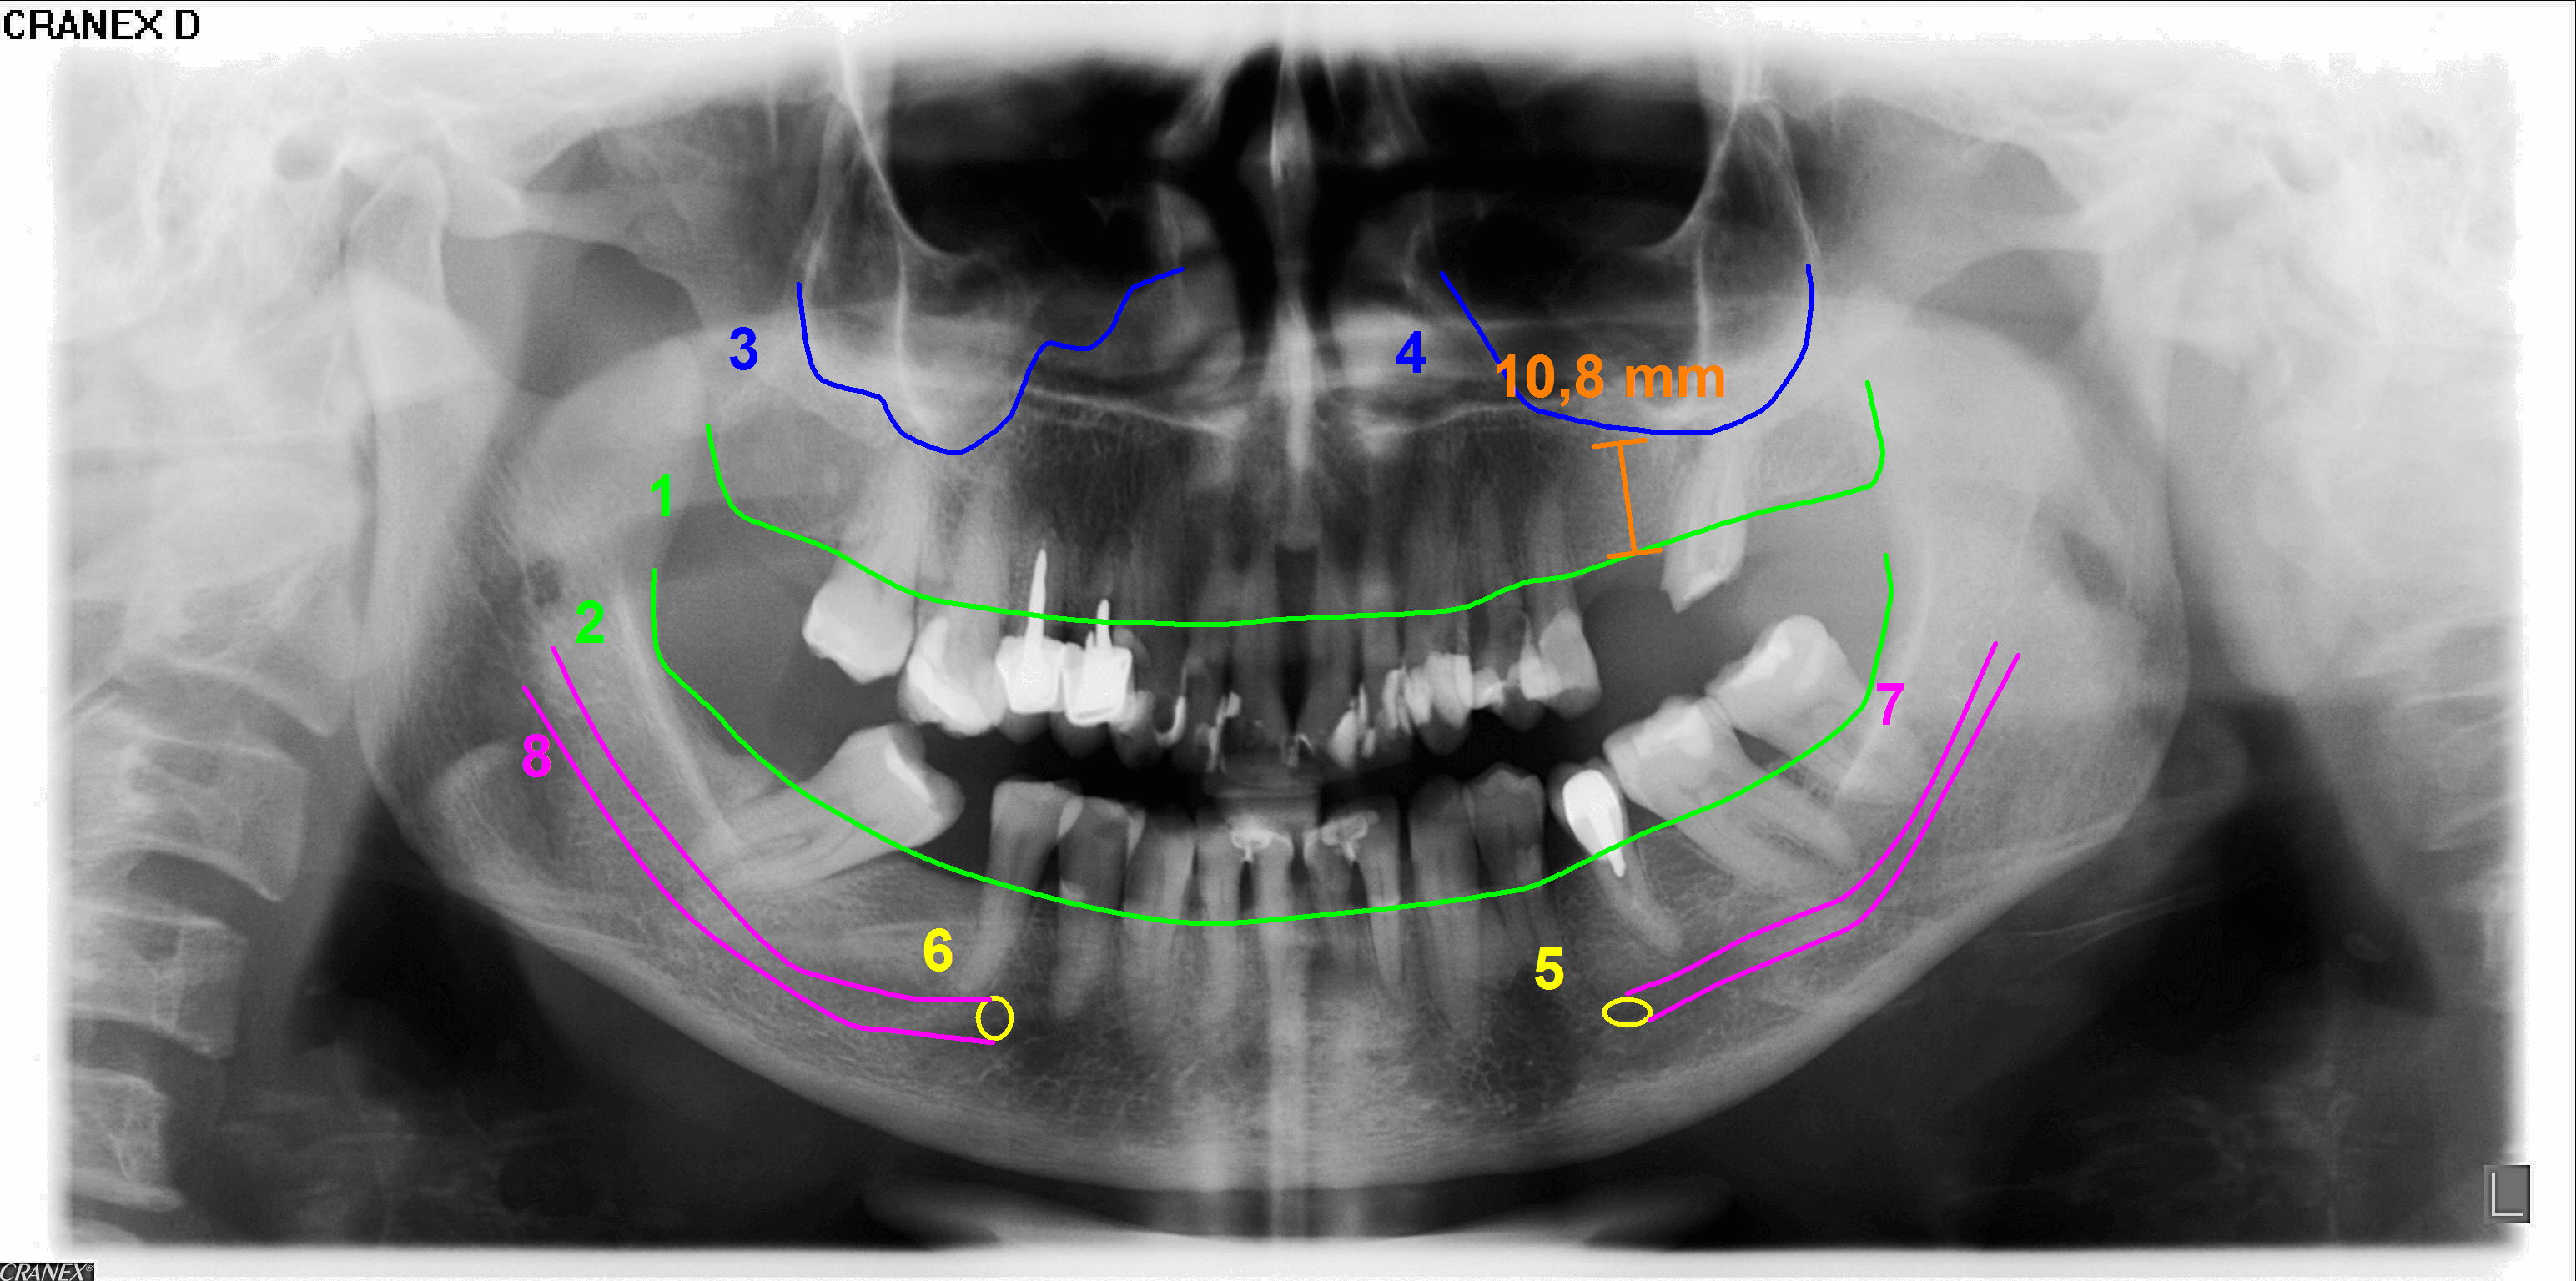

Radiografía panorámica

Radiografía Panorámica para implante

Es la misma radiografía panorámica, obtenida con una ampliación vertical prácticamente constante, donde se proyectan medidas y trazados de las estructuras anatómicas. Sin embargo, recomendamos la tomográfia computarizada Cone Beam que es un importante examen para visualizar y medir tanto la altura como el espesor óseo de la región de interés.